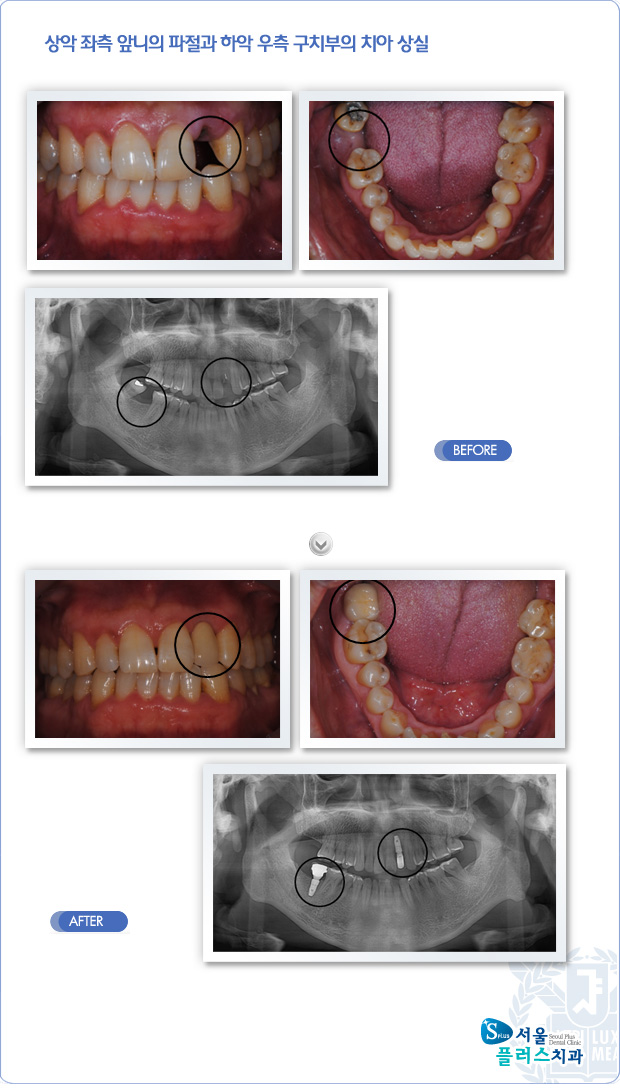

[임플란트] 상악 좌측 앞니의 파절과 하악 우측 구치부의 치아 상실